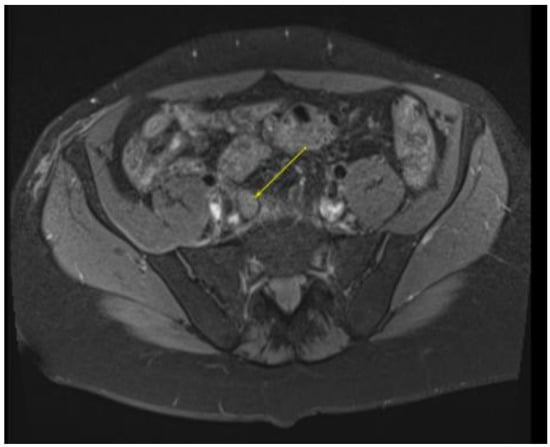

Figure 5.

MRI in the axial view T1 TSE FS pre-showing 22 × 30 mm bilateral inguinal lymph node.

This plan required alteration, as the patient presented again to the hospital three weeks later with worsening symptoms from persistent priapism. This time he also presented with dyspnea and was found to have undergone rapid disease progression, with imaging evidence of new bilateral lung metastases, hepatic metastases, pelvic and inguinal adenopathy, and pubic bone lytic lesions. He was also found to have developed multiple venous thromboemboli with a high clot burden, including bilateral subsegmental pulmonary emboli and thromboses of the right external iliac, left greater saphenous, and bilateral dorsal penile veins (Figure 3, Figure 4, Figure 5, Figure 6, Figure 7, Figure 8 and Figure 9). In addition, there was increased spiculated soft tissue swelling along the dorsal penile shaft and extensive nodularity in the scrotum and inguinal lymph nodes, suggesting tumour invasion of the reproductive organs (Figure 4, Figure 5 and Figure 6). During the physical examination, the penis, scrotum, and pre-pubic areas were dramatically enlarged and firm, with numerous cutaneous lesions consistent with replacement with a tumour. Urology staff were consulted, and they suggested that the disease was not resectable.